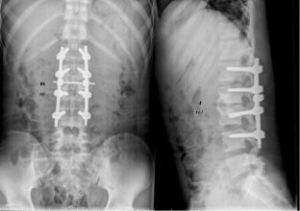

股骨頭壞死的手術治療植骨術:骨移植可刺激股骨頭內血管再生,促進修復和癒合,同時防止股骨頭塌陷,適用於年輕的股骨頭壞死ⅱ期和期股骨頭壞死ⅲ期的股骨頭壞死患者,可延緩病程發展和全髖置換的時間。若結合生長因子或電刺激等促進骨折癒合的方法,可望提高療效。對於鑽孔減壓效果較好的早期股骨頭壞死患者,亦可考慮同時植骨。